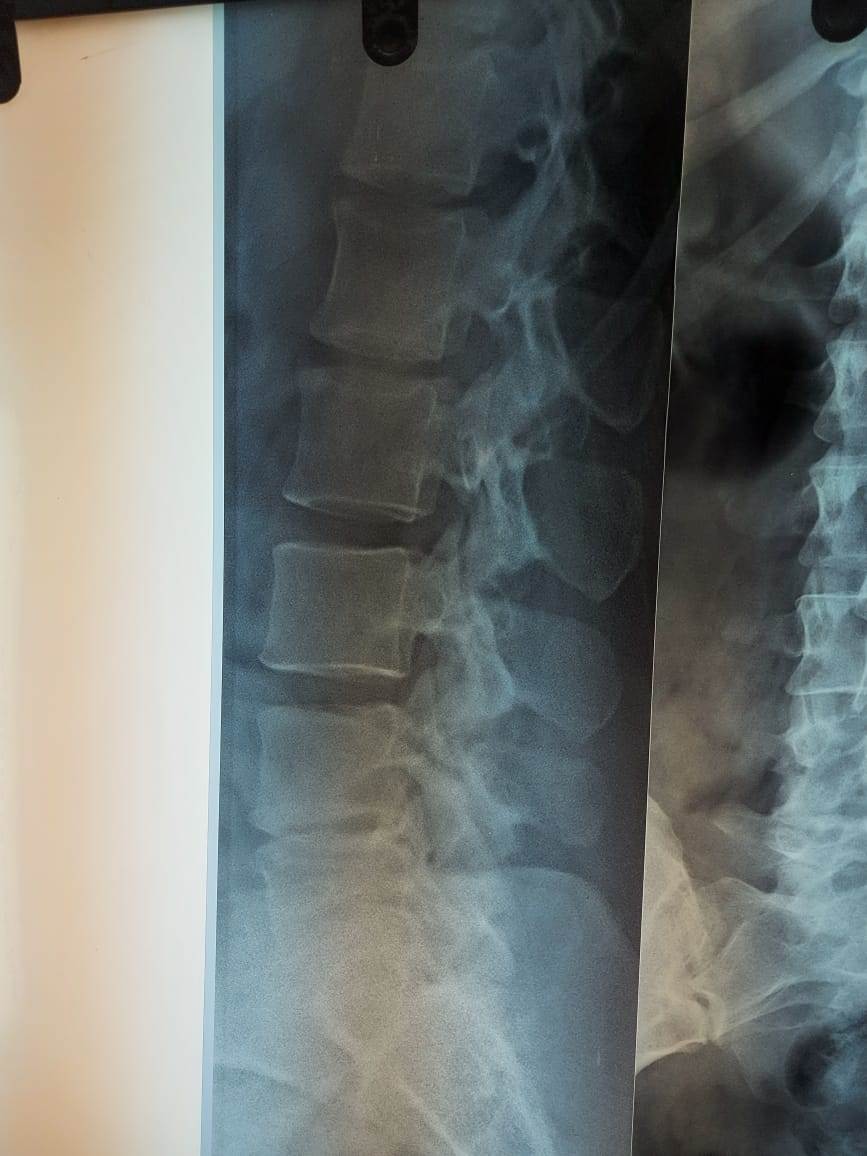

استحدث مستشفى المنيرة العام، خدمات طبية وجراحات جديدة، ولأول مرة أجريت فيه جراحة عمود فقرى، لمريضة تعاني من آلام مزمنة أسفل الظهر، ومنذ 3 أشهر زادت بطريقة شديدة، وتم فحص المريضة وعمل الأشعات اللازمة للتشخيص، وتشخصت بأنها حالة انزلاق فقارى قطني، بين الفقرات القطنية الرابعة والخامسة، والأولى العجزية، وهناك ضاغط علي جذور الأعصاب.

وعلى الفور تم استخراج قرار علاج علي نفقة الدولة، وإجراء جراحة توسيع للقناة العصبية، ومخارج جذور الأعصاب، وتثبيت للفقرات بواسطة أعمدة ومسامير، ودمج للفقرات بواسطة رقعة عظمية ذاتية، وقفص كربوني بين الفقرات القطنية الرابعة والخامسة، واستمرت الجراحة 3 ساعات.